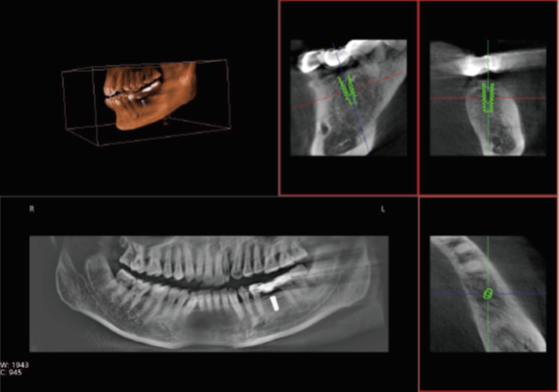

口腔CT是口腔科專用的CT(Cone Beam Computed Tomography), 也就是CBCT,即錐形束CT,采用錐束形X線掃描,可以顯著提高X線利用率,只需圍繞投照體做環(huán)形數(shù)字式投照即可獲取重建所需的全部原始數(shù)據(jù),在計(jì)算機(jī)中重組,進(jìn)而獲得三維圖像。通過(guò)數(shù)據(jù)采集方式的改進(jìn),口腔CT不僅提高了醫(yī)學(xué)影像的掃描分辨率,也將放射劑量降低到了一個(gè)新的水平。那么,哪些口腔治療會(huì)使用到口腔CT呢?

眾所周知,在口腔內(nèi)種植牙齒是十分精細(xì)的手術(shù),沒(méi)有先進(jìn)的可視化影像設(shè)備支持的種植牙手術(shù),就猶如盲人摸象,手術(shù)效果難以預(yù)知。口腔CT影像能測(cè)量牙槽骨的高度和寬度,估計(jì)種植部位,與下頜阻生磨牙相關(guān)的低位下牙槽神經(jīng)管影響頜骨的疾病的病理學(xué)評(píng)估。

正常情況下,牙齒的排列不在一個(gè)平面上, 且具有一定的生理弧度,普通X線往往使圖像相互重疊,使圖片看不清楚。但是,口腔CT的三維成像對(duì)牙體、牙根、牙周膜等微細(xì)結(jié)構(gòu)顯示更加清晰。可以幫助醫(yī)生了解斷根,牙根內(nèi)吸收、根管鈣化、牙根結(jié)石、牙槽骨退縮等情況,能用于根管治療前尋找根管,術(shù)后評(píng)估根管充填情況,評(píng)估牙周炎程度及預(yù)期治療效果等。

正畸治療前的診斷分析是治療成功的重要步驟,口腔CT不僅能提供頭顱側(cè)位和曲斷片的信息,還可以評(píng)價(jià)每個(gè)牙齒的排列位置,牙根傾斜度,牙槽骨垂直向、頰舌向的骨量,骨密度等。用于牙列不齊矯正、牙頜面畸形矯正、牙周病輔助正畸。

口腔CT與全身CT相比,具有分辨率高、X射線輻射小、投照時(shí)間短、費(fèi)用低、應(yīng)用廣泛方便、操作簡(jiǎn)單、可以配合第三方軟件獲得更多信息等優(yōu)點(diǎn)。普愛(ài)醫(yī)療口腔CT使用脈沖透視采集圖像,在保證成像質(zhì)量的基礎(chǔ)上,可有效降低患者吸收的輻射劑量。實(shí)現(xiàn)數(shù)字化三維容積重建,冠狀面、矢狀面、橫斷面的類CT成像效果,重建全景影像,選配牙種植系統(tǒng),滿足牙周、牙根管、口腔矯形矯正、牙種植等臨床病例提供診斷依據(jù)。